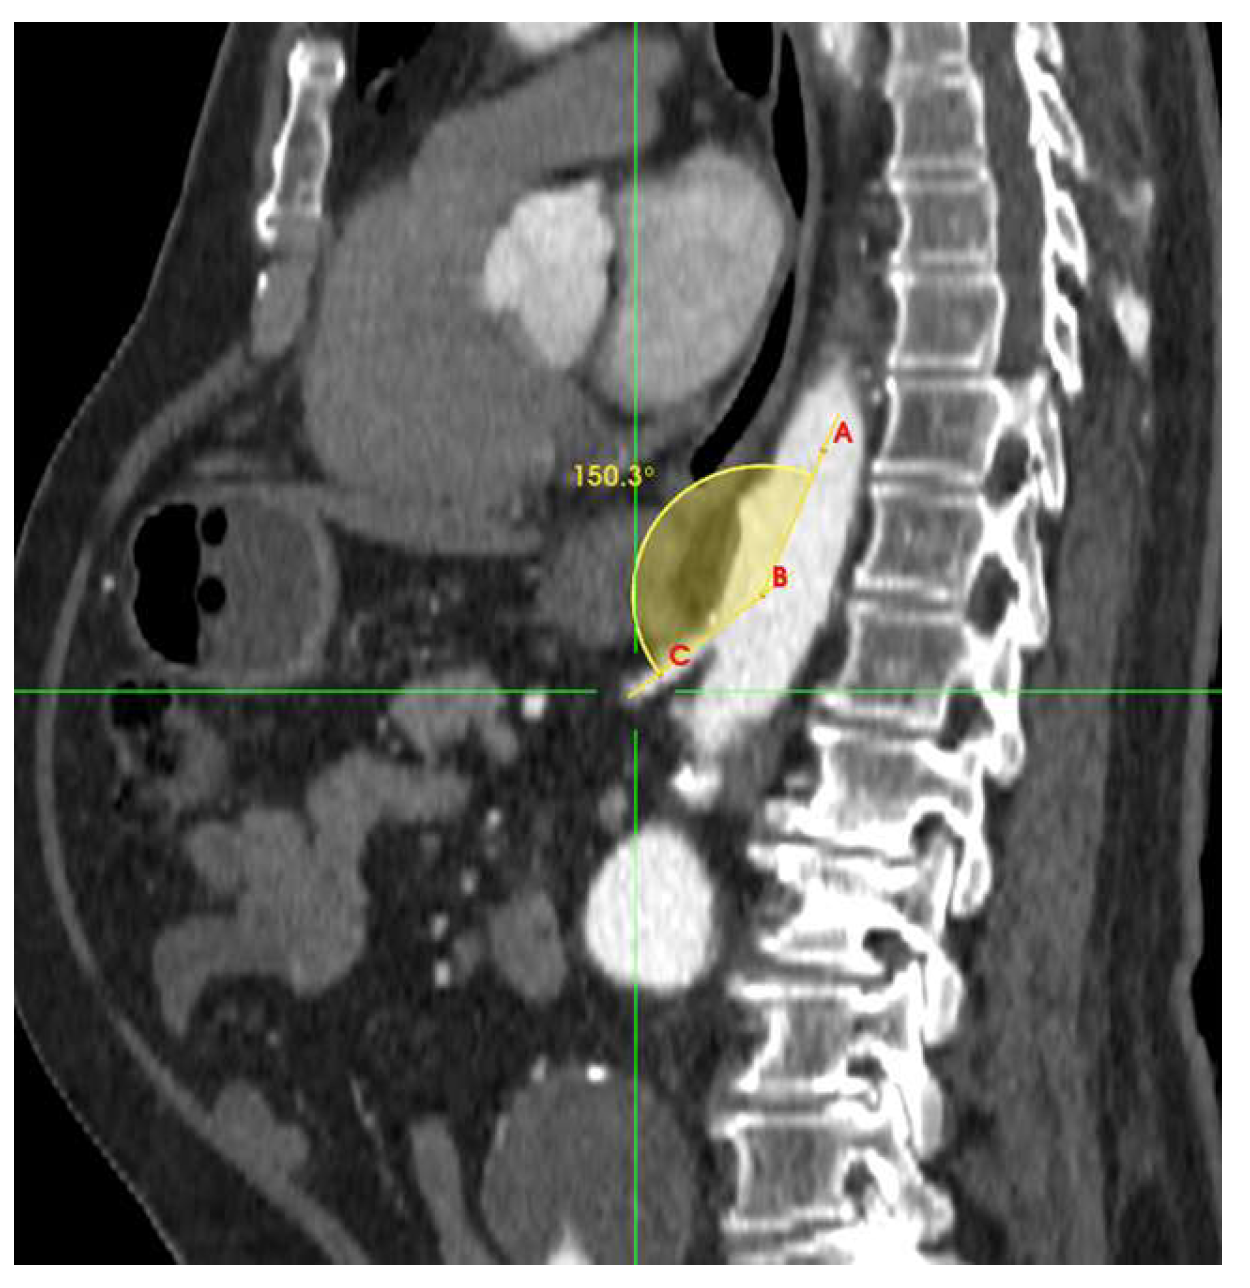

| Takeoff angulation | 0.0184 | ||

| <140° | 9 (31.0) | 41 (56.9) | 0.018 |

| ≥140° | 20 (68.9) | 31 (43.0) | 0.019 |